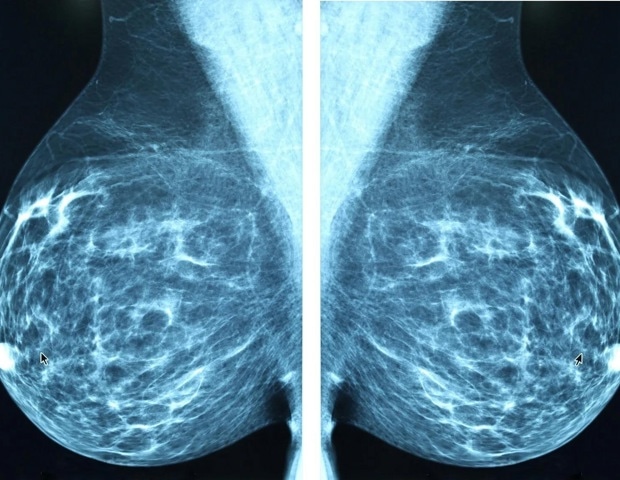

Η ορμόνη estrone και η σύνδεσή της με τον καρκίνο του μαστού στις παχύσαρκες γυναίκες

Ο πιο κοινός και θανατηφόρος τύπος καρκίνου του μαστού στις γυναίκες μετά την εμμηνόπαυση είναι ο καρκίνος του μαστού θετικός σε υποδοχείς οιστρογόνων (ER+). Σύμφωνα με την Joyce Slingerland, MD, PhD, η οποία συντονίζει το πρόγραμμα αλληλεπίδρασης καρκίνου-ξενιστή στο Κέντρο Καρκίνου Lombardi του Πανεπιστημίου Georgetown, οι προοπτικές για τις παχύσαρκες γυναίκες με ER+ καρκίνο είναι ιδιαίτερα ανησυχητικές. Αυτές οι γυναίκες είναι πιο πιθανό να διαγνωστούν με αυτή τη μορφή της νόσου και έχουν 2-3 φορές περισσότερες πιθανότητες να χάσουν τη ζωή τους από αυτήν.